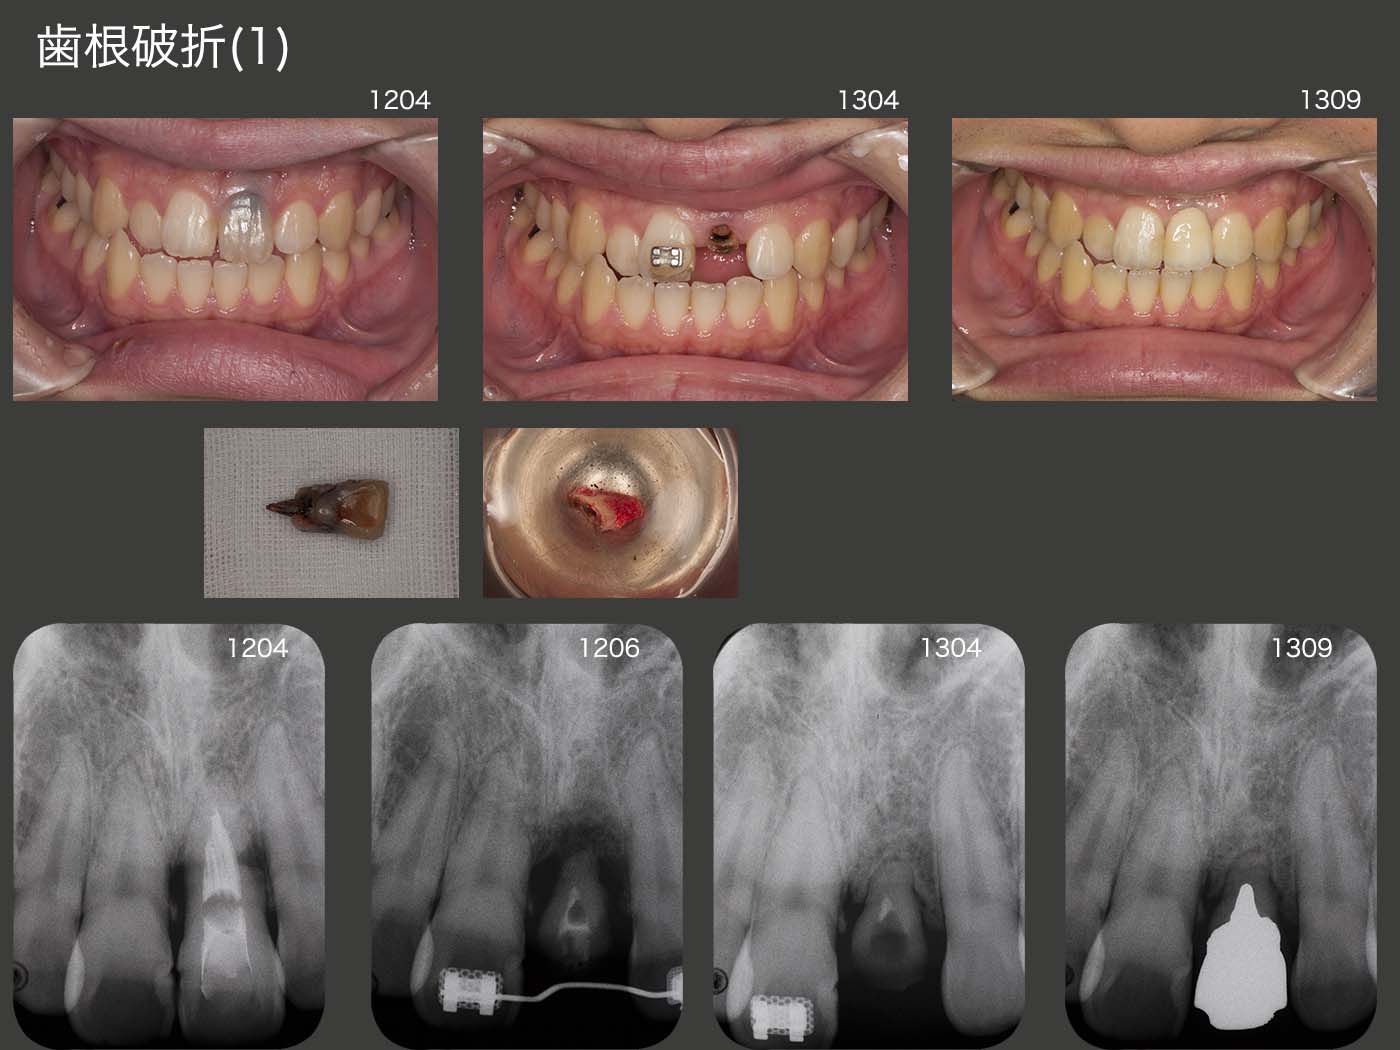

症例3 歯根破折(1)

2012年4月初診、23歳の男性。左上1は10歳の時に転倒して折れた歯を戻したところ、その後およそ2年ごとに腫れを繰り返しているとのこと。最近歯の動揺が大きくなったので来院した。デンタルX線写真から炎症性の歯根吸収らしき像がみられた。通常であれば抜歯し、両側の健全歯を削ってブリッジを装着する症例だが、何とか左上1を保存したいと考えた。

2012年5月に根尖側の抜歯を試みた。何とか愛護的に抜去することができたので、歯肉より上に健康な歯質が得られるところまで挺出させた位置に再植、固定した。約1年間仮歯で経過観察を行い、特に問題がなかったので、2013年9月に硬質レジン前装冠を装着した。歯根が短いため動揺が生じ、ピーナッツ等の固い食品をとれないのが欠点であるが、患者さんは特に不満を訴えていない。